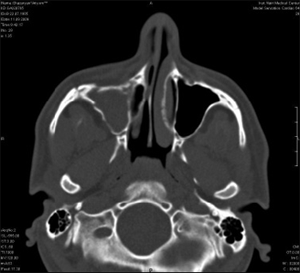

Рис 1. а. Больной до операции.б. КТ лицевого черепа.

Рис 2. КТ верхнечелюстной пазухи

Кожа данной области без видимых изменений. Открывание рта свободное. Слизистая оболочка в области преддверия полости рта справа без изменений. На КТ снимке виден застарелый перелом правой скуловой кости со смещением отломков, носовых костей и передней стенки ВЧП справа (рис.1б), картина хронического травматического гайморита (рис.2).